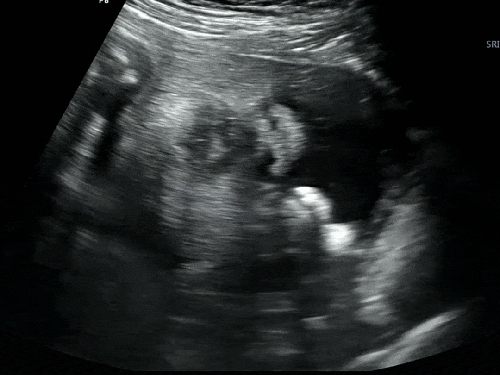

#40. 임신 일기 | 37주 6일 드디어 출산 3일 전 마지막 초음파!

지금은 벌써 출산한지 17일차인 게으른 엄마의 임신 후기 기록하기. 나는 38주 2일에 제왕절개를 하기로 해...